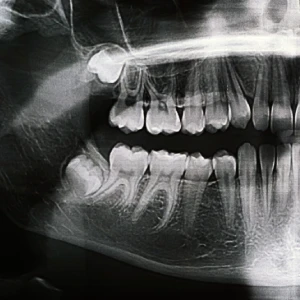

The process usually begins with a full dental examination at a trusted dental office in Brentwood. During this visit, the dentist or oral surgeon will evaluate your teeth and gums and take digital X-rays to check the position of the wisdom teeth. This helps determine whether they are impacted, partially erupted, or likely to create future problems. Based on the results, your provider will explain the treatment plan, discuss sedation options, and give instructions to help you prepare.